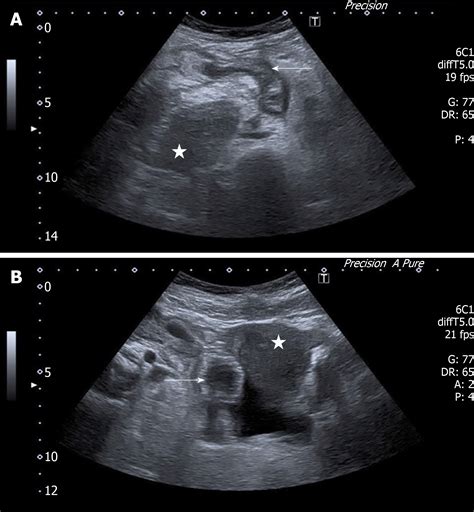

When performing an ultrasound to diagnose appendicitis, radiologists look for several key signs:

• Hyperemia: Increased blood flow to the appendix, which can be detected using Doppler ultrasound, is another sign of inflammation.

• Periappendiceal Fluid: The presence of fluid around the appendix can indicate inflammation or infection.